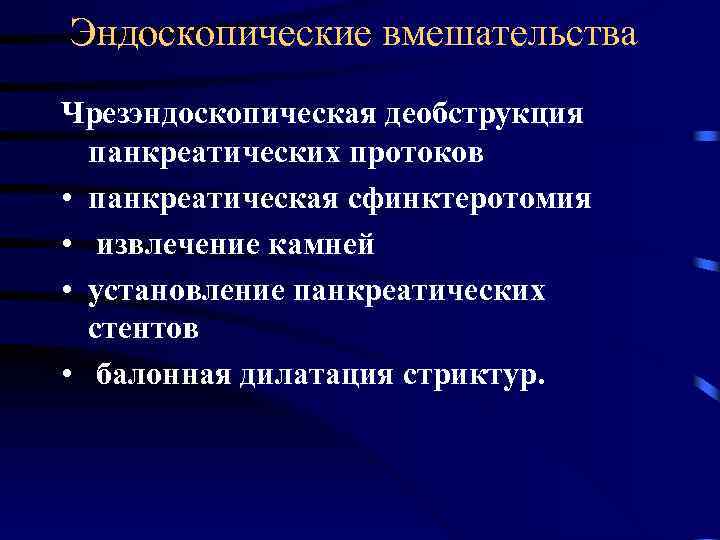

Эндоскопические вмешательства Чрезэндоскопическая деобструкция панкреатических протоков • панкреатическая сфинктеротомия • извлечение камней • установление панкреатических стентов • балонная дилатация стриктур.